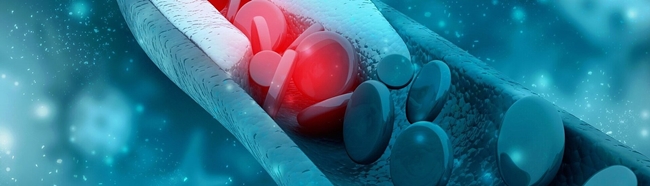

미니어처 피에조 소자(사진. 피아이코리아)

PI Ceramic의 미니어처 피에조 소자는 공간이 협소한 의료 시술에 적합하다. 디스크, 플레이트, 튜브, 구 등 형태가 다양하며 크기가 수 ㎜로 최소 설치 공간에서 높은 유효 힘을 제공한다. PI Ceramic은 테스트 및 패키징에 대한 오랜 노하우로, 고객의 소형 피에조 및 전체 트랜스듀서 조립과 접착을 지원한다. 혈관 내 쇄석술 및 카테터 절제술과 같은 애플리케이션 외에도 미니어처 컴포넌트를 다른 최소 침습적 치료 절차에 사용할 수 있다.